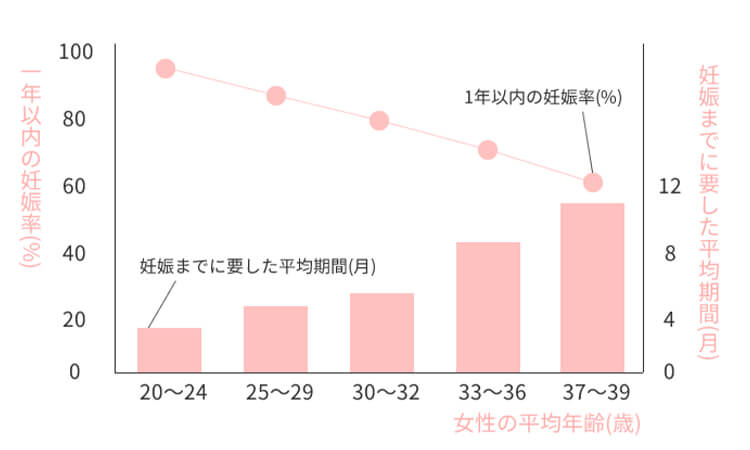

確実に妊娠しない唯一の方法は性交渉をしないことです。ただし、性行為を行っている場合に妊娠の可能性を減らす方法はたくさんあります。

米国では10代の妊娠率が少なくとも25年間低下し続けている。専門家らは、これは性的に活発な十代の若者がコンドームを使用しているためだと考えています。